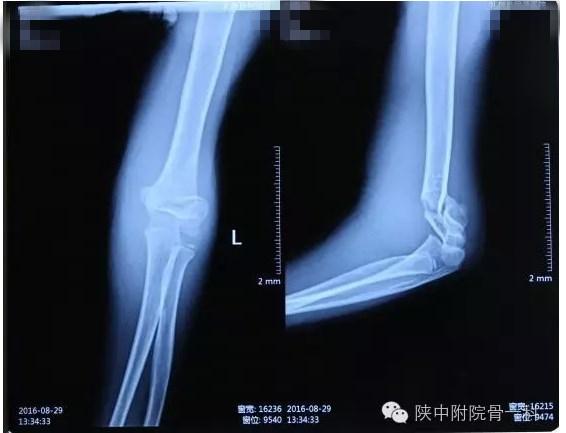

病案一:患儿XX,女,8岁,摔伤后左肘关节疼痛伴活动受限3小时入院。

诊断:Gartland Ⅱ型骨折

急诊行闭合手法复位克氏针内固定,术后X线片(下图)